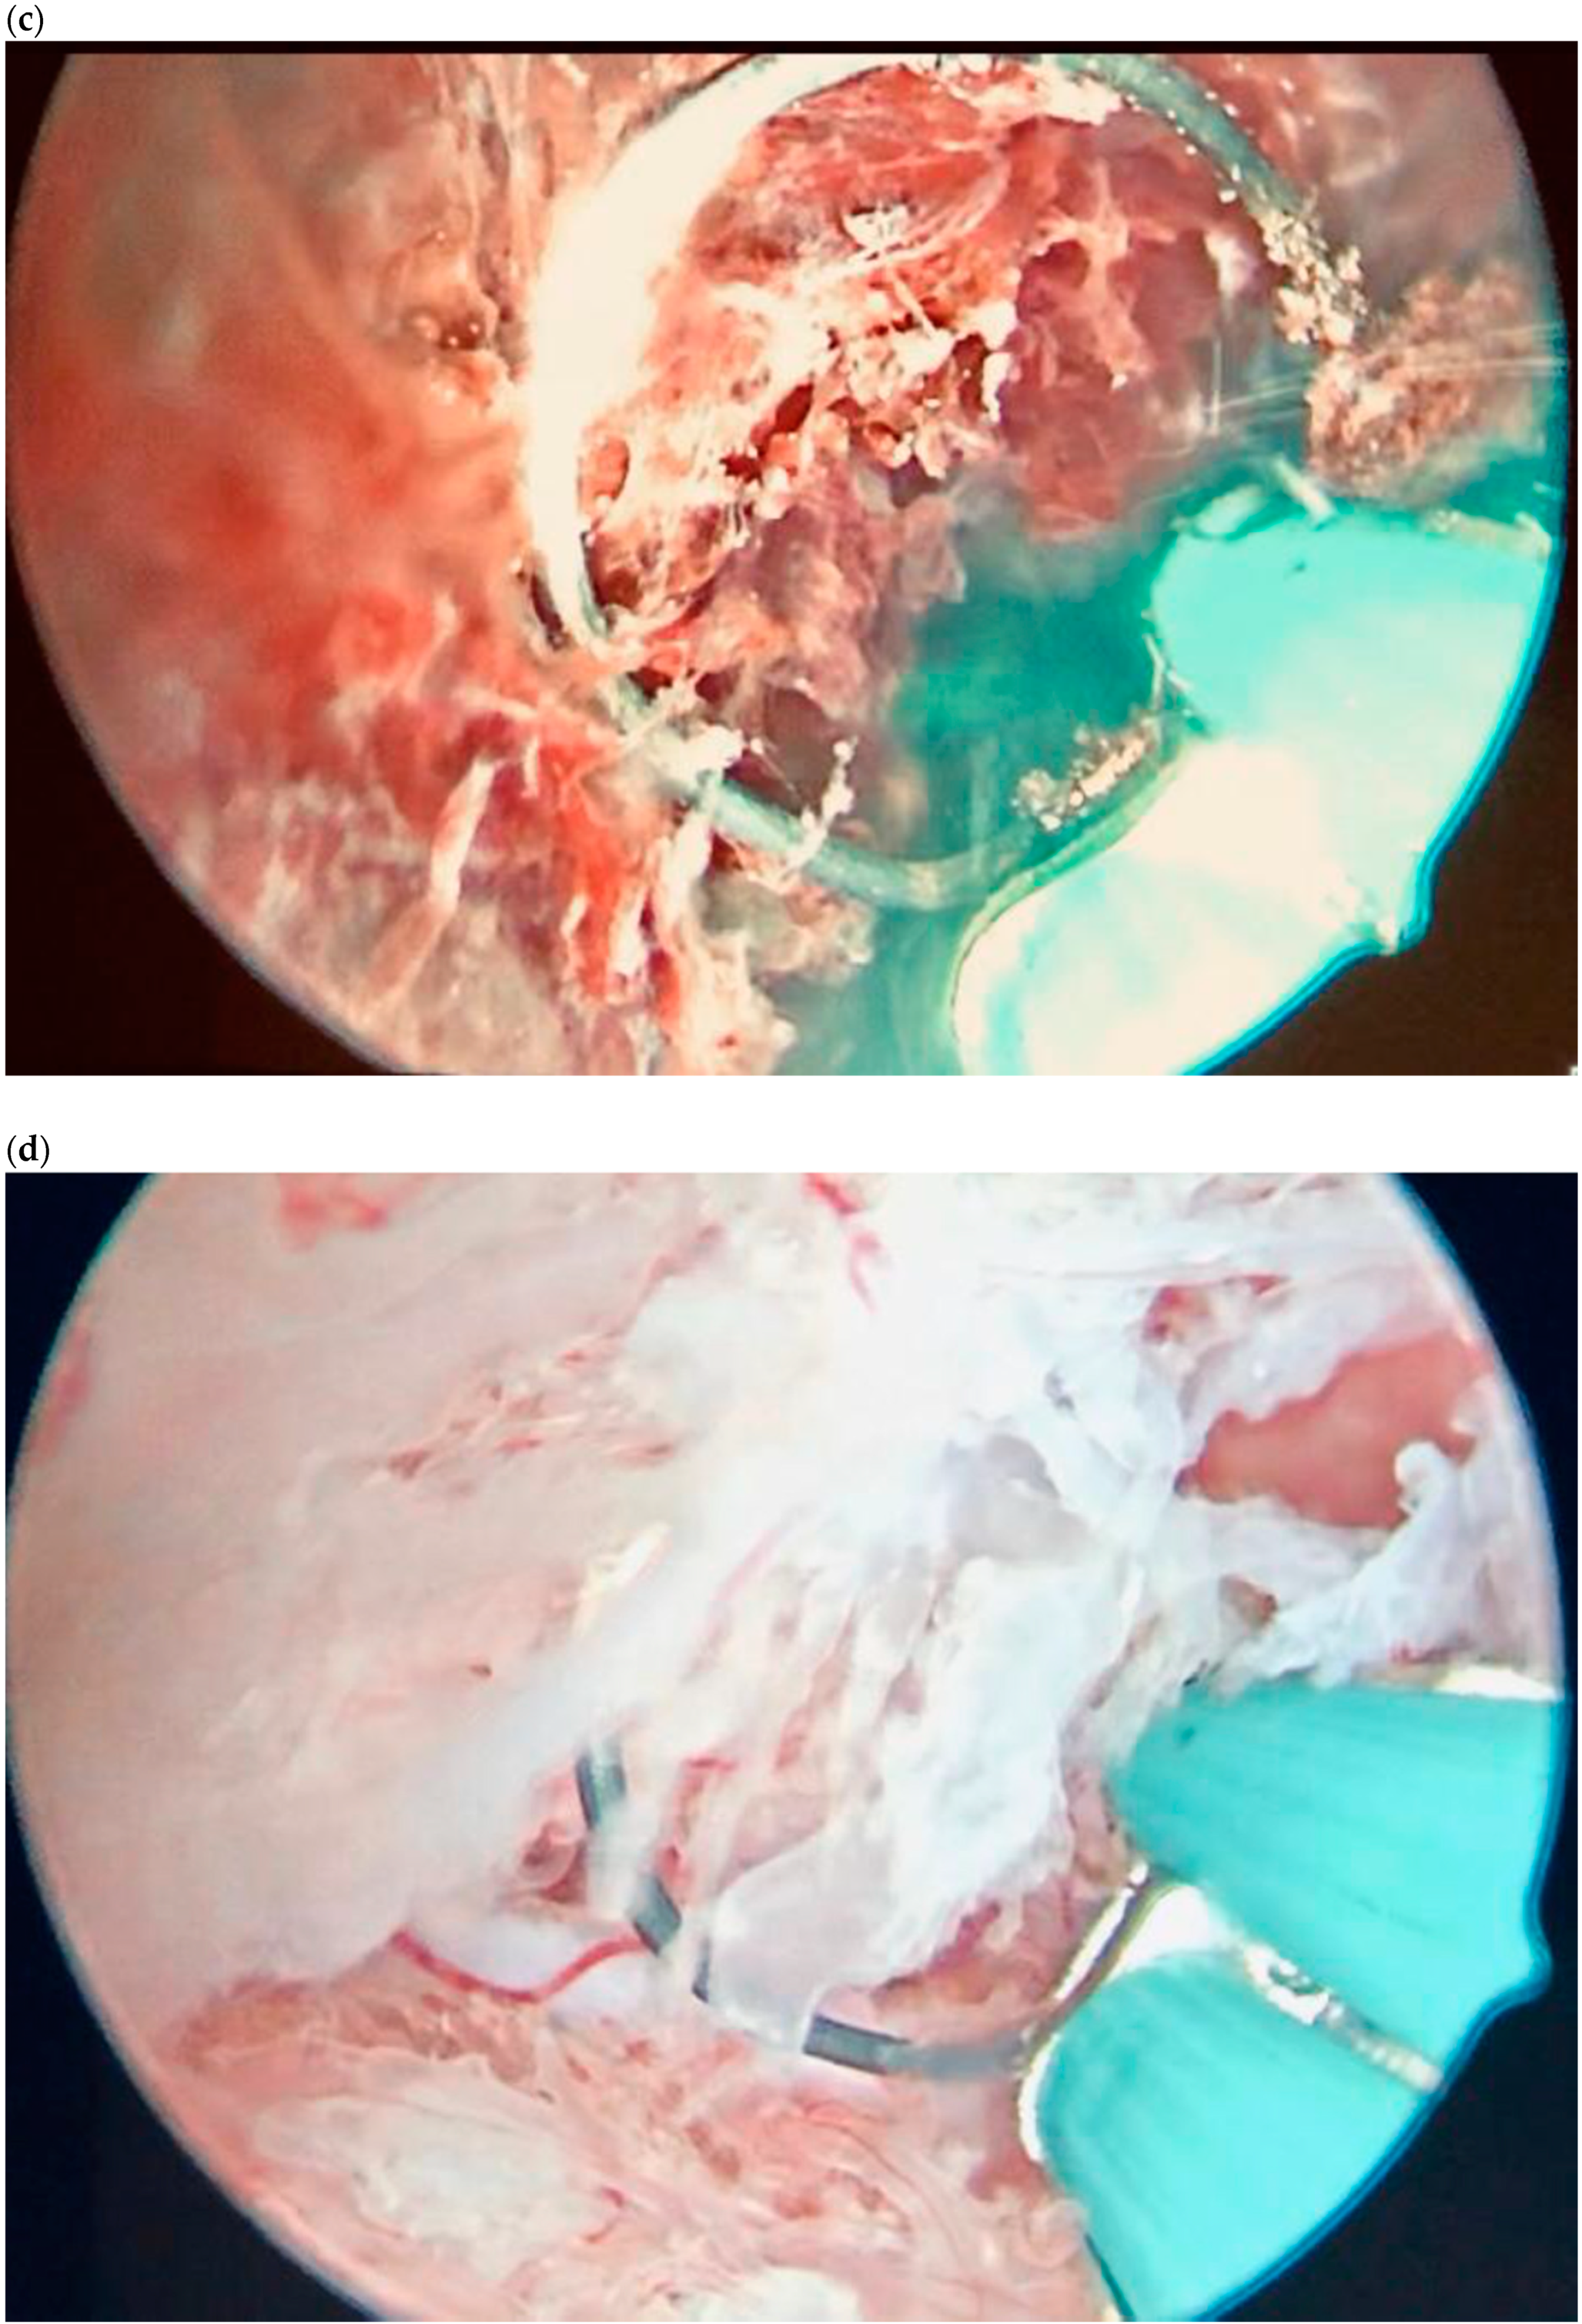

| Case 2 | Asymptomatic | 6 + 6 | 10,862 | GS 20 × 19 mm; with embryo | Hys: 1st step: CP resection by twizzle; IC Foley catheter 2nd step: vessels electrocoagulation by bipolar twizzle | Reoperation (hys) due to tissue residues and cervical laceration Complete resolution |

| Case 6 | Vaginal bleeding | 6 | 4274 | GS 5.4 × 5 mm with embryo | MTX IM 50 mg/m2 of body surface + Hys: CP resection by twizzle | Complete resolution |

| Case 1 | Asymptomatic | 6 | 119,900 | GS 14 × 16 mm | MTX IM 50 mg/m2 of body surface + Misoprostol 200 µg rectal + Hys (two times) + Curettage | Complete resolution |

| Case 2 | Asymptomatic | 6 + 2 | 31,647 | GS 12 × 10 mm | Mifepristone 600 mg + Misoprostol 400 mcg + Hys: reseptoscopy | Complete resolution |

| Case 3 | Asymptomatic | 7 + 1 | 131,000 | GS 9 × 10 mm | Hys: twizzle and minireseptor + Curettage | Complete resolution |